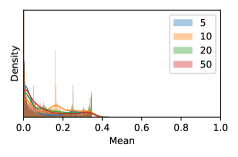

To model how different classifiers will respond to a given input , we assume that the prediction from classifier is sampled from a beta distribution that is characterized by two parameters by and . We further assume that is fixed to the same constant value for all ’s. Under this assumption, each input can be described by ( can be calculated since is fixed), easing further analysis. The Severity Level (SL) of the case represented by image can be characterized by the parameter . The larger the value of , the more severe the case of is. When and are close, the case is ambiguous as the distribution shifts towards being symmetric (i.e. signifying much disagreement among classifiers) rather than being one-sided (i.e. consensus among classifiers that is negative or positive). We provide a set of examples in Figure 2 and also Figure S.8 in the supplementary materials showing how the beta distribution can be used to capture diverse predictions given by an ensemble learner.

In contrast, the MC-dropout method showed the worst overall performance among the three, as it can be seen from the high ratios of SL0 examples among the uncertain negatives in Figure 4. The histograms in Figure 2 provides another perspective to look into the phenomenon, where a decent proportion of MC-dropout model’s predictions on SL0 inputs entailed low confidence (far from 0 or 1), which from another angle explained why MC-dropout was less specific in terms of lower FNP; many no-DR inputs (i.e. SL0) were erroneously assigned high uncertainty by MC-dropout models.

As discussed in Section 5.1 and Section 5.3 in the main paper, the mean metric and the stacking ensemble will have better performance in the precision (specificity) on the ambiguous data. Here, more detailed results are shown in Figures S.3 & S.6 and Table S.1. Figures S.3 & S.4 show the histograms of the uncertainty score for Kaggle-DR and Messidor-2 datasets that are the in-distribution (i.d.) dataset in our experiment and FigureS.5 & S.6 show the histograms for ImageNet and CIFAR-10 datasets, which is the o.o.d. datasets in our experiment. Each group of histograms contains results from the three evaluated ensemble methods (stacking ensemble, MC-dropout and TTA) and the three uncertainty metrics (mean, var and kl). Additional detailed results not displayed in Figure 4 can be found in Table S.1, which shows the proportion of the data of different SLs varies across different . For comparison, we also included in Table S.1 the results from single learners, and the proportions of data of different SLs (before any selection was made).